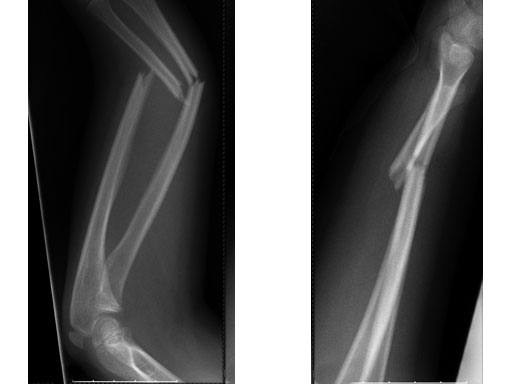

Case 1: Transverse forearm, shaft fracture (22D/4.1), 9-year-old girl.

Case provided by Theddy Slongo, Bern, Switzerland